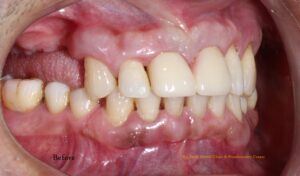

A 50-year-old male patient from New Zealand arrived at our clinic seeking to replace his upper teeth. He had recently returned to Nepal for a 20-day visit and had already explored treatment options at other dental facilities. Unsatisfied with both the proposed treatment plans and the costs, he came to us with his desires and expectations. We listened attentively, taking careful note of his needs. He had already had X-rays taken at the request of a previous dentist.

On his first visit, we performed a thorough examination of his teeth and gums. He had upper back teeth missing and remaining upper front teeth were mobile, whereas his lower teeth were not mobile but required gums treatment. We explained his condition of oral hygiene and treatment required. We presented him with all available options, including removable and fixed prostheses. He opted for a fixed prosthesis with upper arch replacement using 4 dental implants (All-on-4). We also discussed different implant brands and types, and he selected Bredent Copasky implants (Fast & Fixed). Additionally, we offered various prosthetic options for permanent prosthesis, and he chose a hybrid denture.

Fig: Pre-operative extra-oral, intra-oral photographs and X-ray